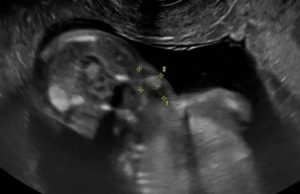

Врожденное кистозное новообразование. Нажмите для увеличения

Так как во время беременности заболевание никак не проявляется и не сопровождается никакой симптоматикой, то диагностировать его можно только при плановом УЗИ. Необходимо проходить обследование у квалифицированного специалиста ультразвуковой диагностики, потому что кисту яичника у плода легко перепутать с патологиями кишечника (такие случаи встречались).

Внеплановое УЗИ можно сделать в течение 32 недели беременности, а также на 40-й, перед родами.

Ультразвуковое исследование позволяет не только диагностировать наличие заболевания, но также его локализацию, размеры, эхоструктуру. Также УЗИ дает возможность отслеживать изменения размеров кисты как в сторону увеличения, так и ее регресс.

Благодаря УЗИ можно заранее обнаружить патологию. Киста яичника у плода при подобном обследовании выявляется часто.

Врождённая киста может достигать десяти сантиметров. На УЗИ образование хорошо заметно в нижней части живота.

Параметры кисты данного органа варьируются от 1 до 10 сантиметров. Врачи пришли к следующему умозаключению — чаще всего образования формируются у зародыша на 26 неделе беременности. Обнаружить кисту плода можно во время ультразвукового обследования.

Она имеет круглую форму, располагается внизу брюшины зародыша.

Киста яичника у плода — образование, которое сложно рассмотреть во время беременности. Для этого врачи прибегают к ультразвуковому обследованию. Данный метод позволяет им рассмотреть образование в увеличенном виде на мониторе.

Современная ультразвуковая диагностика позволяет не только определить наличие опухоли у зародыша, но еще оценить ее структуру и размеры. На основе этой информации врач может составить прогноз. Чаще всего заболевание проходит спонтанно, за несколько месяцев после родов.